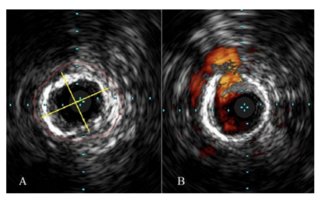

Shammas and colleagues discuss how treatment of infrapopliteal arteries can be challenging due to the presence of medial calcinosis and fibrotic rings.